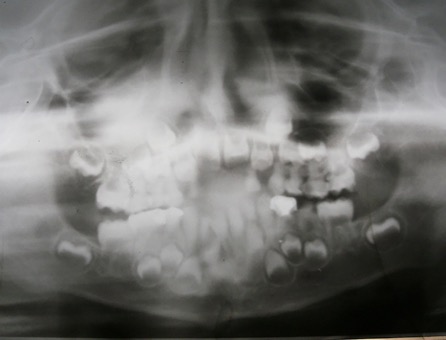

El examen clínico intraoral reveló alteración de la estructura y color de las piezas primarias, atrición y pérdida de la dimensión vertical (Figura 2). Radiográficamente se observó la presencia de coronas con marcada constricción cervical y raíces cortas (Figura 3). Presentaba alto riesgo cariogénico, por la presencia de lesiones de caries activas y dos restos radiculares, sumado a la anomalía estructural de la dentina (riesgo biológico específico) y bajo riesgo gingivoperiodontal. El riesgo socio-económico era alto por provenir de una familia con marcadas limitaciones económicas. Luego de la anamnesis, examen clínico y radiográfico, e interconsulta con el médico de cabecera se estableció el diagnóstico de DI Tipo I asociado a OI tipo I. Se planificó un tratamiento integral y preventivo con los objetivos de devolver forma y función, y proteger y evitar el desgaste de los tejidos conductas que pudieran interferir con el tratamiento.

Figura 3: Radiografía panorámica año 2007

En la radiografía panorámica de control del año 2015 se observó la progresiva obliteración del conducto radicular en el grupo incisivo superior e inferior y en los primeros molares permanentes; presentado los premolares en erupción, un conducto radicular anormalmente amplio en toda su longitud (Figura 8). En la del año 2018 se visualizó la continua aposición de dentina a nivel radicular que obliteró en forma casi total los conductos de la mayoría de las piezas dentarias, a excepción de los segundos molares inferiores (Figura 10).

Debido el alto porcentaje de abscesos periapicales, producto de la obliteración progresiva de los conductos radiculares, es fundamental el monitoreo radiográfico periódico en pacientes con DI.1 Los controles con radiografías panorámicas fueron realizados en el 2007, 2010, 2015 y 2018, sin registro de patologías pulpares periapicales.